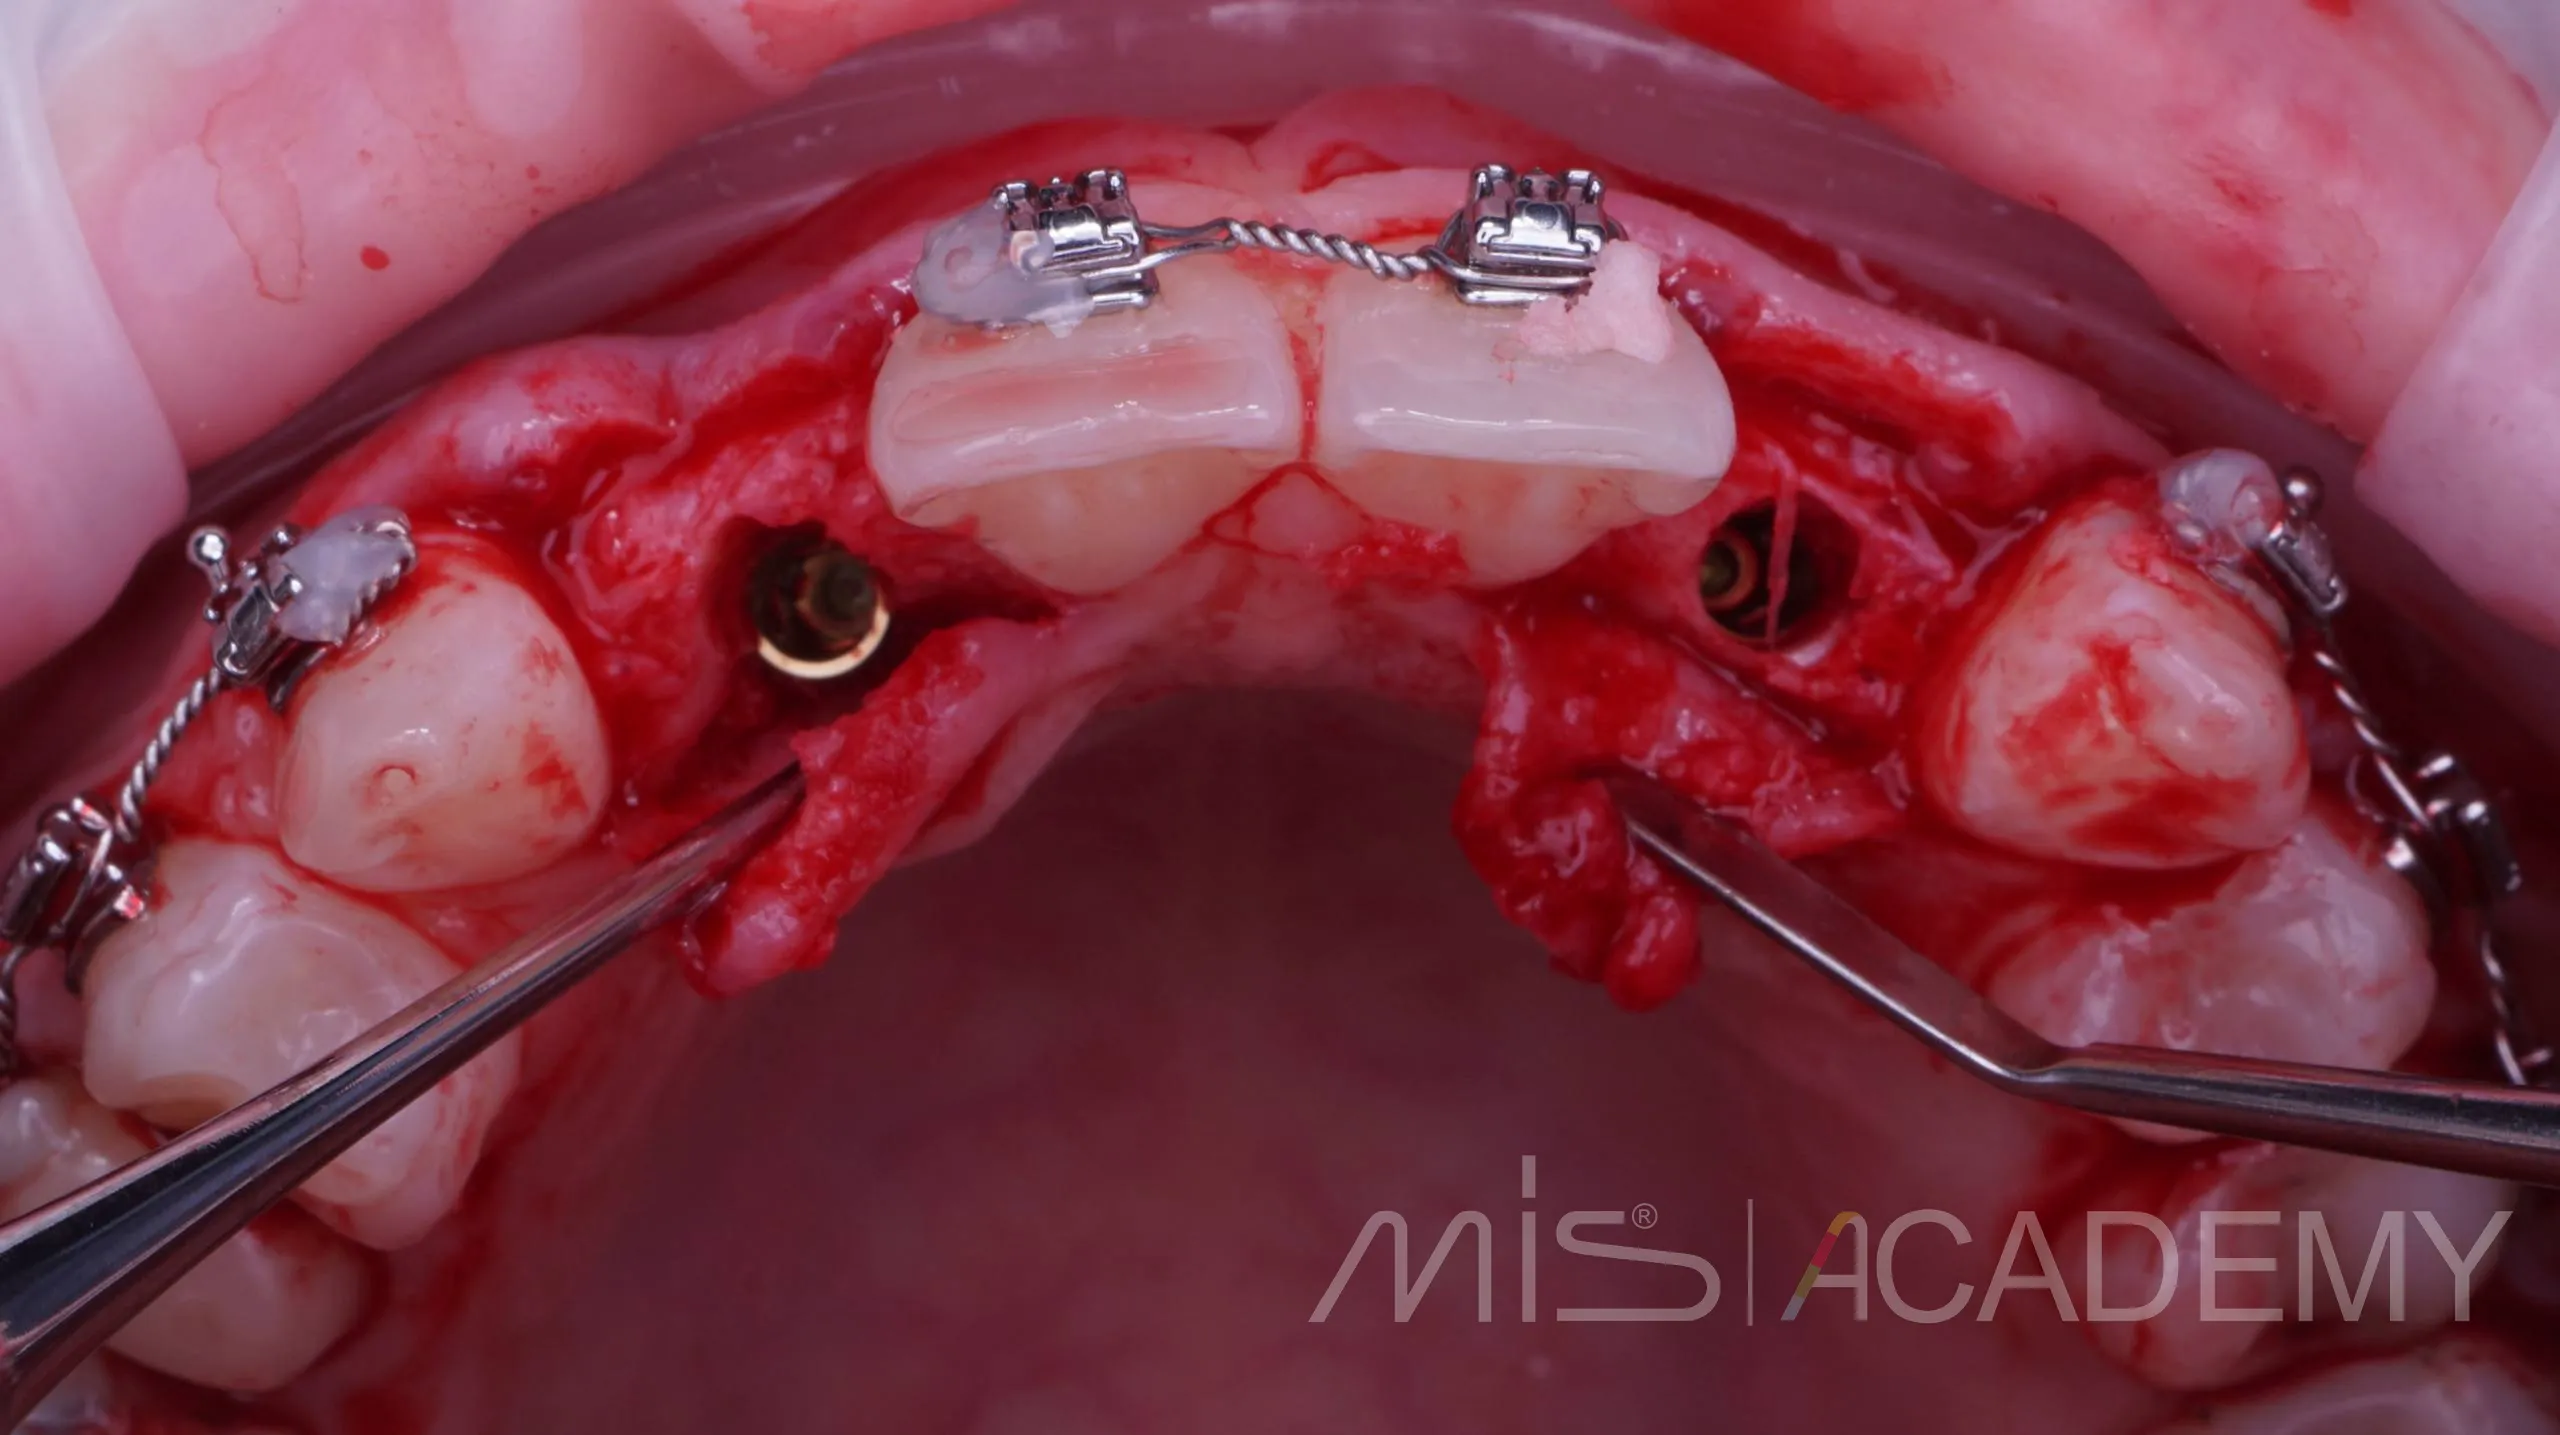

Небольшой рекол в 1 год после имплантации в область адентии двоек на верхней челюсти

— Имплантация MIS C1 узкая платформа.

— Connect абатменты.